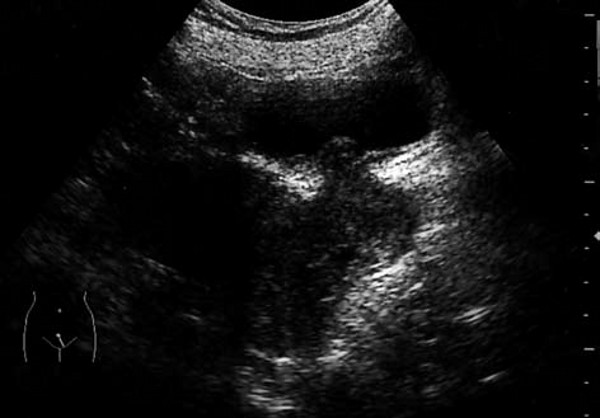

患者,女,28岁。因接触性不规则阴道流血3个月来院就诊。超声检查报告显示宫颈增大,形态不规则,有一6.0 cm×4.5cm×5.1cm低回声区,境界不清,回声分布不均匀。CDFI:见稀疏血流。

超声提示:宫颈实质性占位病变(符合宫颈癌)。

病理诊断:子宫颈大细胞非角化性鳞形细胞癌,浸润宫颈壁全层。